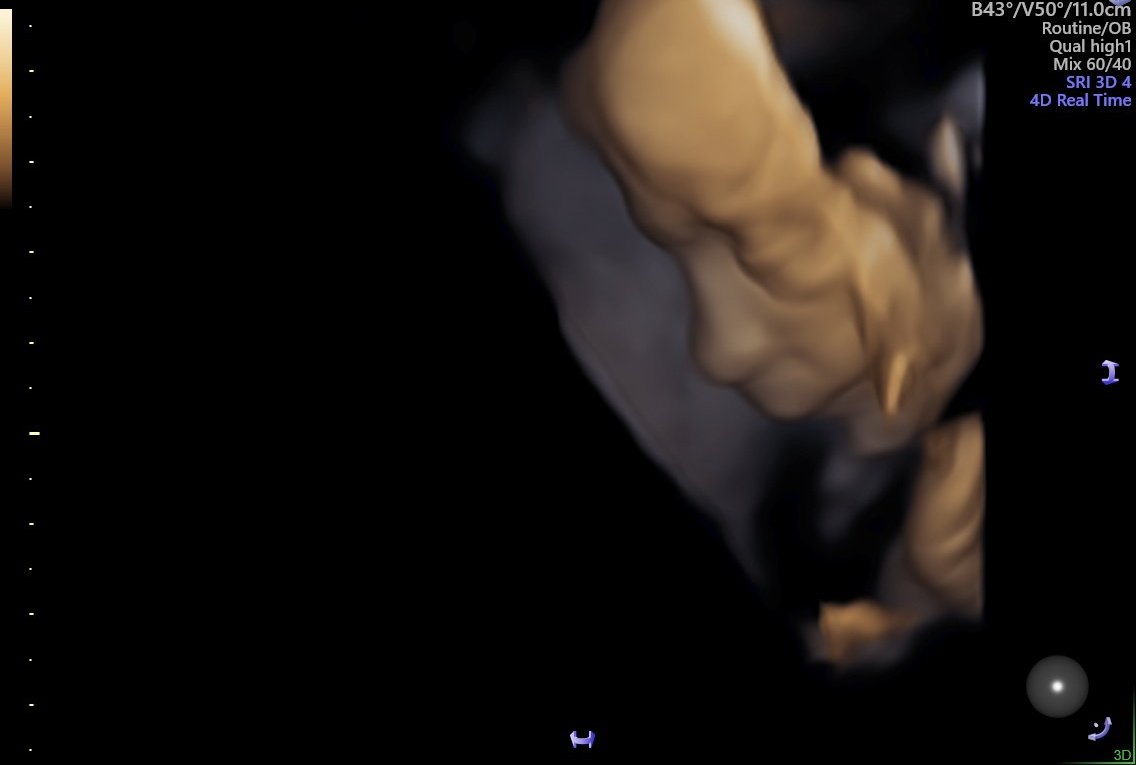

Ето я и моята кукличка от днес Докторката каза, че ще се окаже голяма мислителка 😁 460гр, 21+6 съм